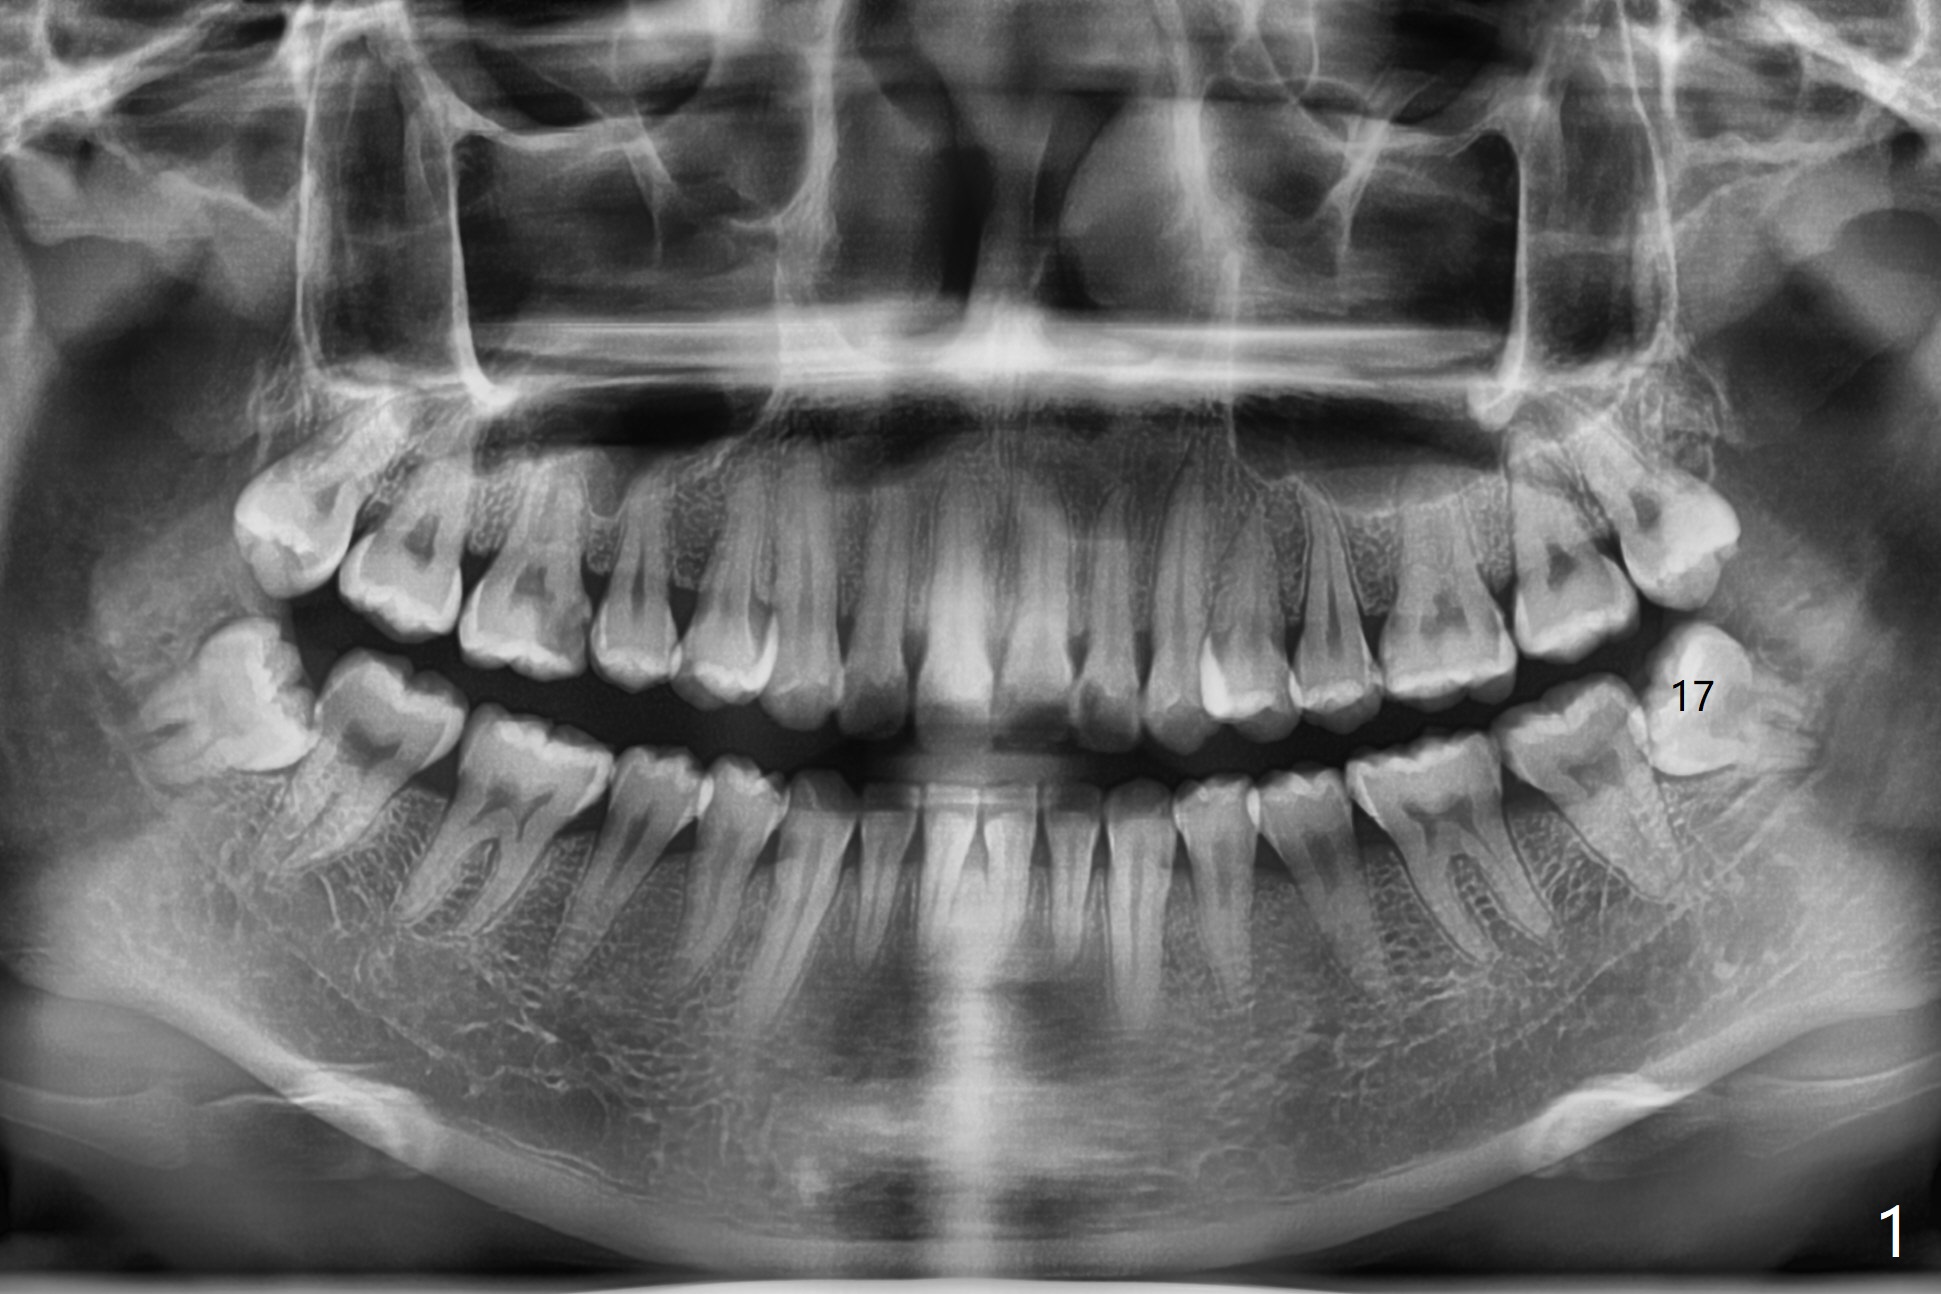

A 24-year-old woman with poor oral hygiene presents to clinic requesting extraction of the tooth #17 (Fig.1). The tooth is removed after multiple sectioning. One half of collagen plug is placed in the bottom of the socket (Fig.2 C, while 1 cc of Bond Apatite in the coronal portion of the socket (A). The other half of the collagen plug is placed on the top of the cement before suturing with 4/0 PGA. The patient feels pain when the tooth is wiggled heavily. But the Inferior Alveolar Canal is not exposed when the tooth is out. Return to Plug Cement Xin Wei, DDS, PhD, MS 1st edition 07/14/2020, last revision 07/14/2020